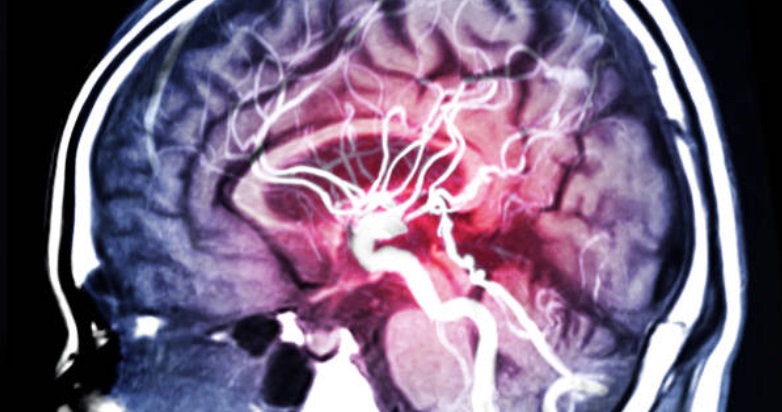

L'ictus ischemico è una delle principali cause di morte e disabilità, causato dalla morte neuronale dovuta all'interruzione del rifornimento di glucosio e ossigeno al cervello. Le cellule nervose sono particolarmente vulnerabili a questo tipo di condizione e, senza un tempestivo ripristino del flusso sanguigno, l'ischemia può portare a una cascata di eventi che culmina nella morte cellulare. Attualmente, i trattamenti come la trombectomia endovascolare e la trombolisi intravenosa hanno migliorato gli esiti clinici, ma le opzioni per una neuroprotezione efficace restano limitate.